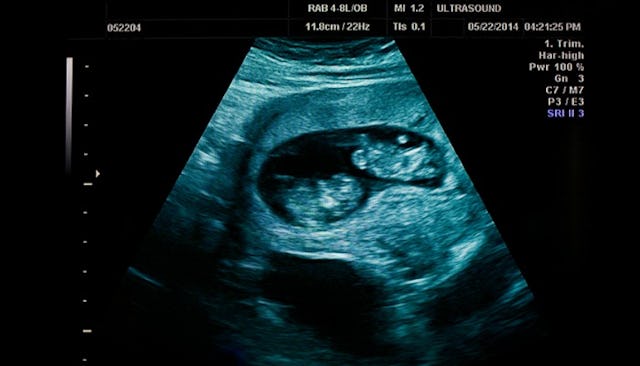

Joe and I started to hysterically laugh. We were beyond excited. She showed us where Twin B was. This was the baby I had seen the week before with the very strong heartbeat. This baby was measuring perfectly, and his or her little heart was flickering away on the screen. I was thrilled. The doctor then showed us Twin A, who she let us know was measuring a bit smaller.

There was much excitement and joy in the room. The doctor took several pictures and labeled them. She gently let us know that there was a possibility that due to the smaller size, Twin A might not make it. But she was very confident that Twin B was doing great. We made an appointment for the following week, and then we would go from there.